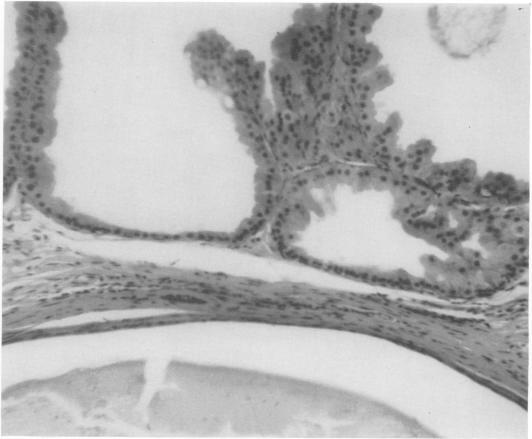

Can breast carcinoma be anticipated? A follow-up of benign breast biopsies.

Ann Surg. 1968 Jun;167(6):829-38. doi: 10.1097/00000658-196806000-00003.